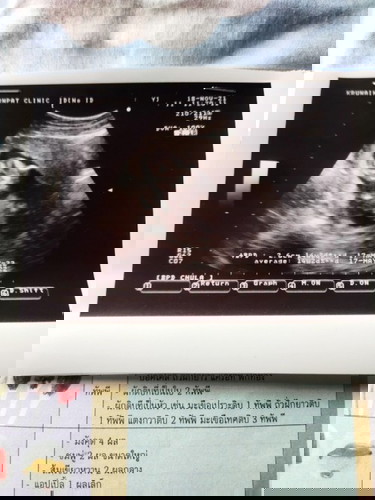

ขอดูภาพอัลตร้าซาวด์ของคุณแม่14วีคได้ไหมคะ

15weekค่ะ น้องน่าจะนอนค่ำหน้า เพราะไม่บอกรายละเอียดอะไรเลยค่ะ